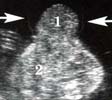

Echographiquement : -Absence permanente de visualisation de la vessie alors que

-Haut appareil urinaire normal

-Quantité de LA normale

-Muqueuse vésicale saillante au niveau de la région sous-ombilicale

Association possible d’autre élément de célosomie inférieure :

-omphalocèle